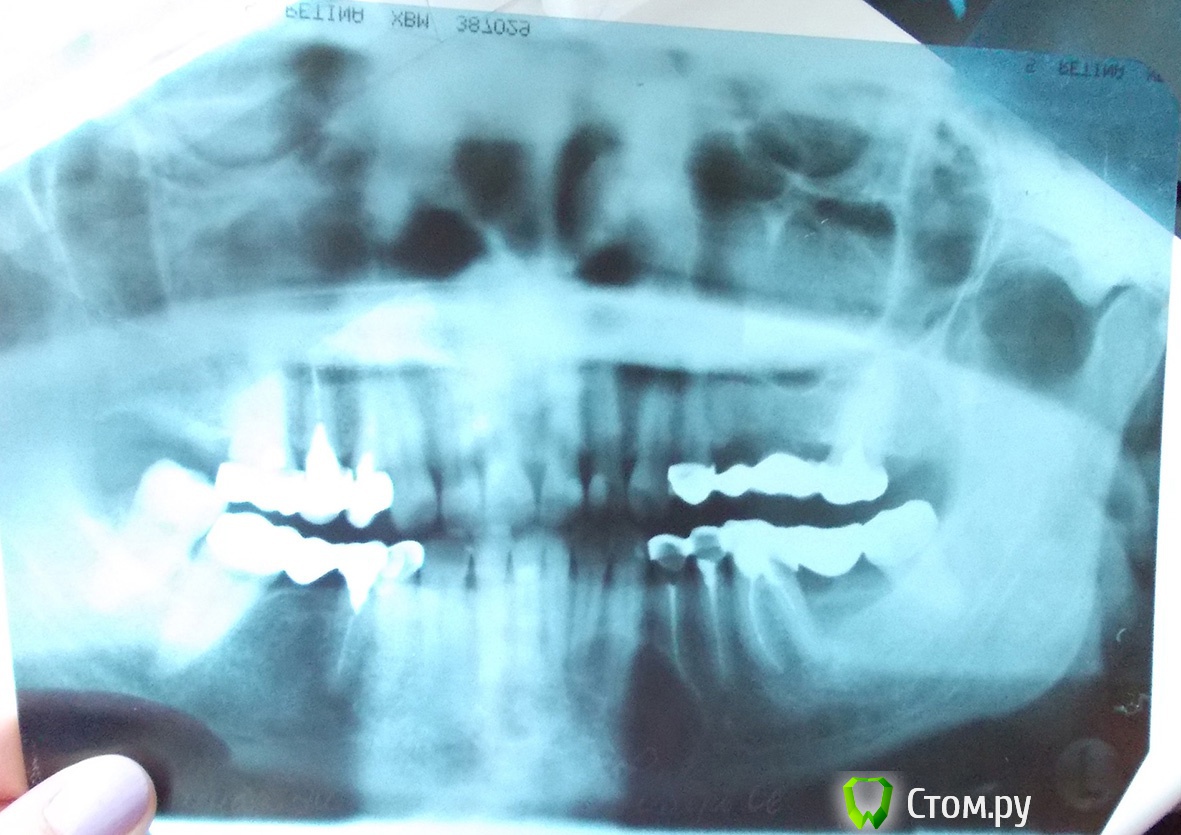

Korel Опубликовано 21 сентября, 2014 Поделиться Опубликовано 21 сентября, 2014 Только не хочется пилить 6 здоровых зубов. Есть другой способ? Прежде чем что то "пилить" , нужно определиться с диагнозом. Я думаю , что для начала следует сделать КТ, затем возможно пункцию, а только после этого определяться с планом дальнейших мероприятий. Ссылка на комментарий

Korel Опубликовано 21 сентября, 2014 Поделиться Опубликовано 21 сентября, 2014 Дежурный врач от отделения ЧЛХ в приемном покое больницы сегодня ответила на мое предложение обследовать новообразование (это мой стоматолог сказала, что они вначале должны обследовать), что надо вначале вырезать, а потом отправлять на гистологию. Так все-таки есть способ вначале взять пункцию? Для начала, успокойтесь. Вы "ждали" 7 лет, сейчас горячку пороть не вижу необходимости)) Сделайте (первый шаг) КТ, покажите доктору, выложите КТ на форум , это займёт , думаю, день-два, что не критично. Ссылка на комментарий

Helenka Опубликовано 23 сентября, 2014 Автор Поделиться Опубликовано 23 сентября, 2014 Сделайте (первый шаг) КТ, покажите доктору, выложите КТ на форум , это займёт , думаю, день-два, что не критично. Сделала КТ, врач сказала что мне уже надо думать о челюсти, а не о зубах. Напугала. Думаю, теперь вопрос стоит по другому - Куда бежать делать операцию? Уважаемые специалисты, подскажите, пожалуйста, где найти врача, который лечит такое намного чаще, чем раз в месяц. С программой на диске не справилась, нашла только один jpg, небольшого размера. Сам диск 500 мб. Ссылка на комментарий